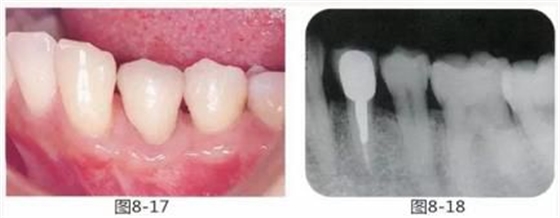

圖8-17 最終佩戴修復(fù)體時(shí)的狀態(tài)。完成修復(fù),對(duì)鄰牙的牙周組織幾乎無(wú)影響。

圖8-18 佩戴修復(fù)體時(shí)的X光照片。